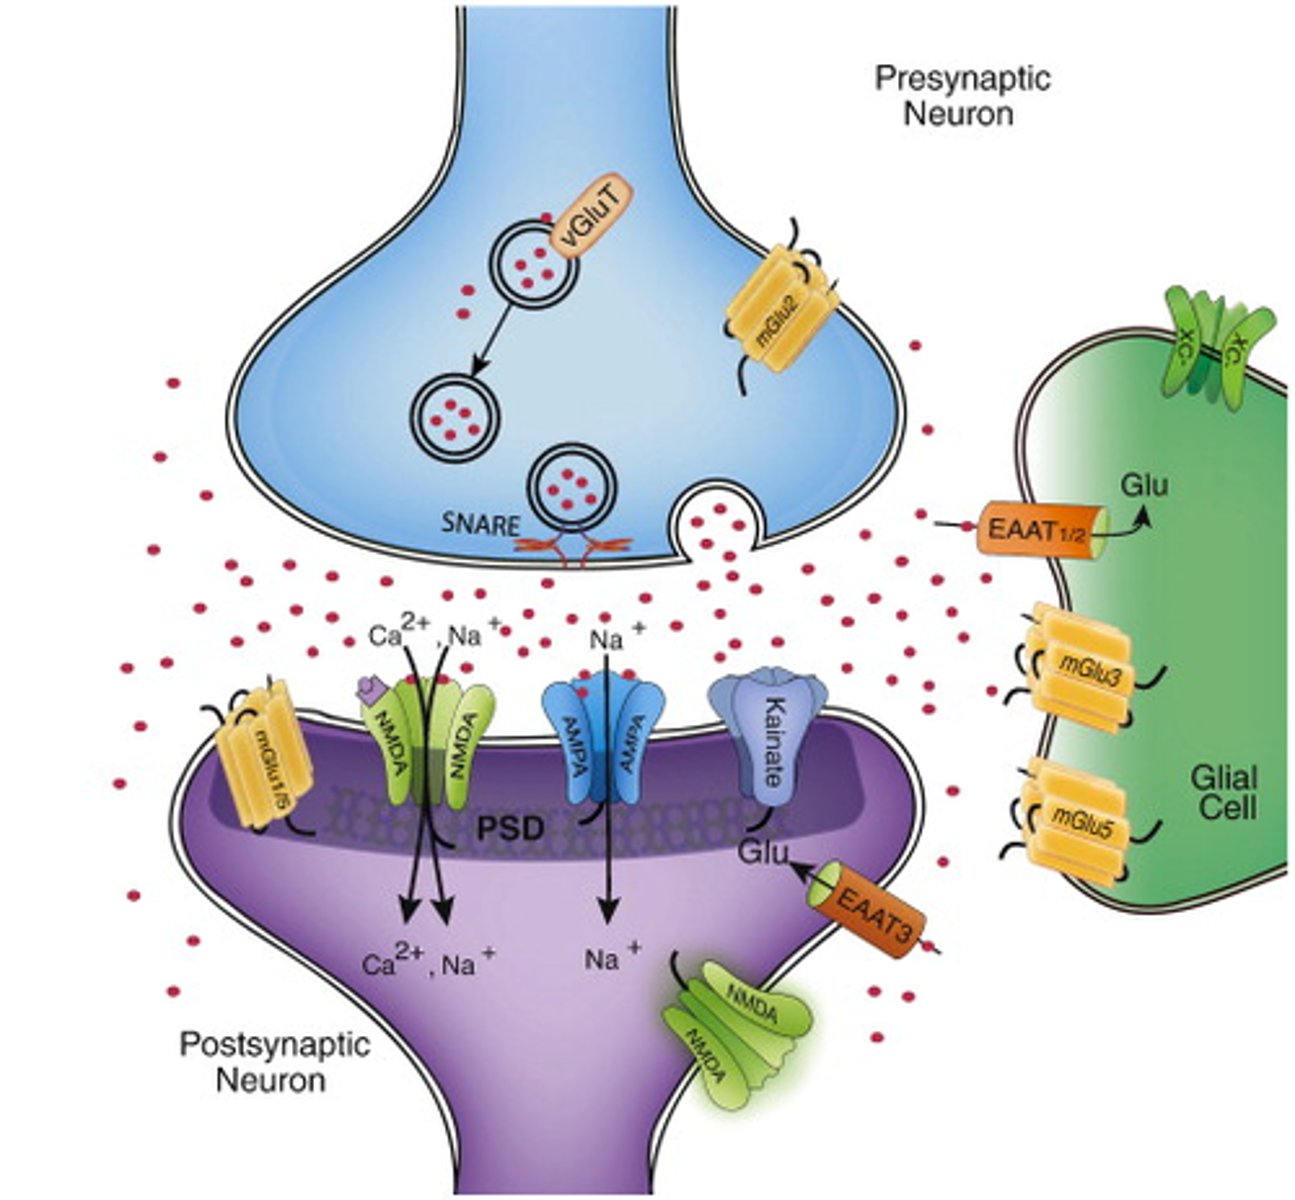

Glutamate

main excitatory neurotransmitter in the nervous system; participates in relay of sensory information and learning

Glial cells

play a role in the formation of myelin and the blood-brain barrier, response to injury, removal of debris, and enhancing learning and memory

Reuptake

reabsorption of a neurotransmitter by the sending neuron after it completes its work